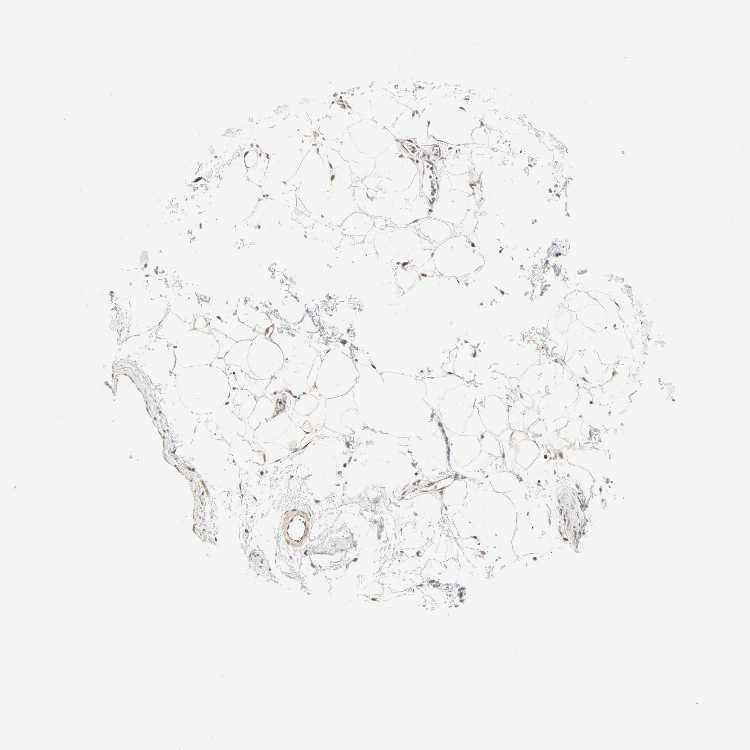

SOFT TISSUE 1 - Antibody stainingi

Antibody staining in the annotated cell types in the current human tissue is reported as not detected, low, medium, or high, based on conventional immunohistochemistry profiling in selected tissues. This score is based on the combination of the staining intensity and fraction of stained cells.

Each image is clickable and will lead to virtual microscopy that enables deeper exploration of all samples and also displays staining intensity scores, fraction scores and subcellular localization as well as patient and tissue information for each sample.

Antibody HPA007267

Fibroblasts Low